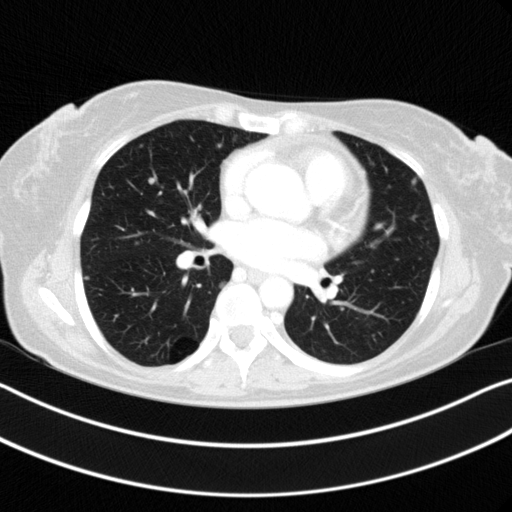

Original VENOUS CT scan

Full window (WL 1023.5, WW 4095 β†’ Low βˆ’1024, High +3071)

Actual HU range: [-1024.0, 1256.0]

Lung window (WL -600, WW 1500 β†’ Low βˆ’1350, High +150)

Actual HU range: [-1024.0, 150.0]

Mediastinum window (WL 40, WW 400 β†’ Low βˆ’160, High +240)

Actual HU range: [-160.0, 240.0]